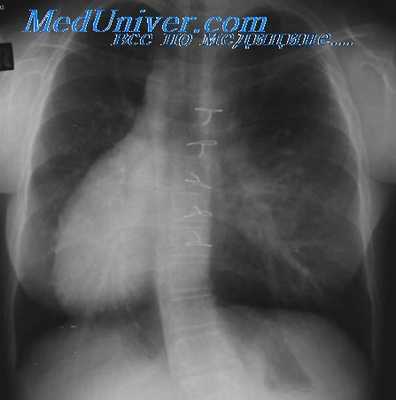

Ангиокардиографическое исследование во всех случаях целесообразнее начинать с введения контрастного вещества в венозный желудочек. При этом можно получить сведения о локализации этой камеры, ее внутренней архитектонике, о типе взаимоотношения между магистральными сосудами, наличии или отсутствии стеноза ЛС в изолированном виде или в сочетании с дефектом МЖП (у больных с гемодинамикой тетрады Фалло и сбросом крови справа налево). При получении фазы левограммы уточняют локализацию и анатомию артериальных отделов сердца (нет или есть сброс крови в правые отделы сердца при изолированных дефектах перегородок).

У больных с множественными пороками, кроме этого, контрастное вещество следует вводить в ЛП или в артериальный желудочек, чтобы исключить существование единственного желудочка, открытого общего атриовеитрикулярного канала, и в ПП— для выявления возможной атрезии трикуспидального клапана и общего предсердия.

Радиоизотопное исследование печени и селезенки необходимо проводить, так как трудно установить диагноз множественных пороков сердца, топическая диагностика которых остается иногда неясной даже после проведения повторных ангиокардиографий. Признаки висцеральной симметрии, обнаруженные при сканировании в виде срединного расположения печени или отсутствия селезенки, должны Косвенно свидетельствовать о тяжелых множественных пороках, не поддающихся хирург гической коррекции.